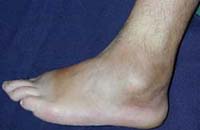

Se realizó biopsia a los seis meses de su aparición que demostró tejido blanquecino friable, de superficie micropapilar con volumen de aproximadamente 5 cm a la observación macroscópica. Al examen microscópico se observó tejido fibroso denso con múltiples formaciones nodulares llenas de material eosinófilo fibrinoide, rodeadas por inflamación granulomatosa a cuerpo extraño, concluyente de tofo gotoso. Luego de presentar trauma leve presentó limitación para la extensión del tobillo. Seis meses posteriormente apareció masa en codo de consistencia blanda con dolor, eritema y calor local. Antecedente de tabaquismo 1 paquete/año y bebedor de cerveza cada mes sin llegar a la embriaguez. No refirió clínica de compromiso articular en el momento de aparición de las masas. Seis meses luego de la aparición de la primera masa presentó artritis de rodillas y de primera metatarsofalángica pie izquierdo. Al examen físico se encontró codo izquierdo con masa irregular de consistencia blanda, en relación con el olécranon de 2×2 cm. Signos de sinovitis activa en rodillas y cuello de pie bilateral, masa de consistencia blanda en relación con la patela de 2×2 cm con calor local, eritema y masa indurada en primera metatarsofalángica derecha con masa de similares características en primera metatarsofalángica derecha. Cicatriz a nivel de maléolo externo izquierdo (Figura 2B). Se practicó niveles de ácido úrico 8 mg/dl. Se inició tratamiento con allopurinol y colchicina, presentando al mes mejoría de la artritis a nivel de articulaciones descritas.

Figura 2 B. Se aprecia cicatriz en la región posterior del maléolo externo del pie izquierdo, luego de resección, donde se encontró el tofo.